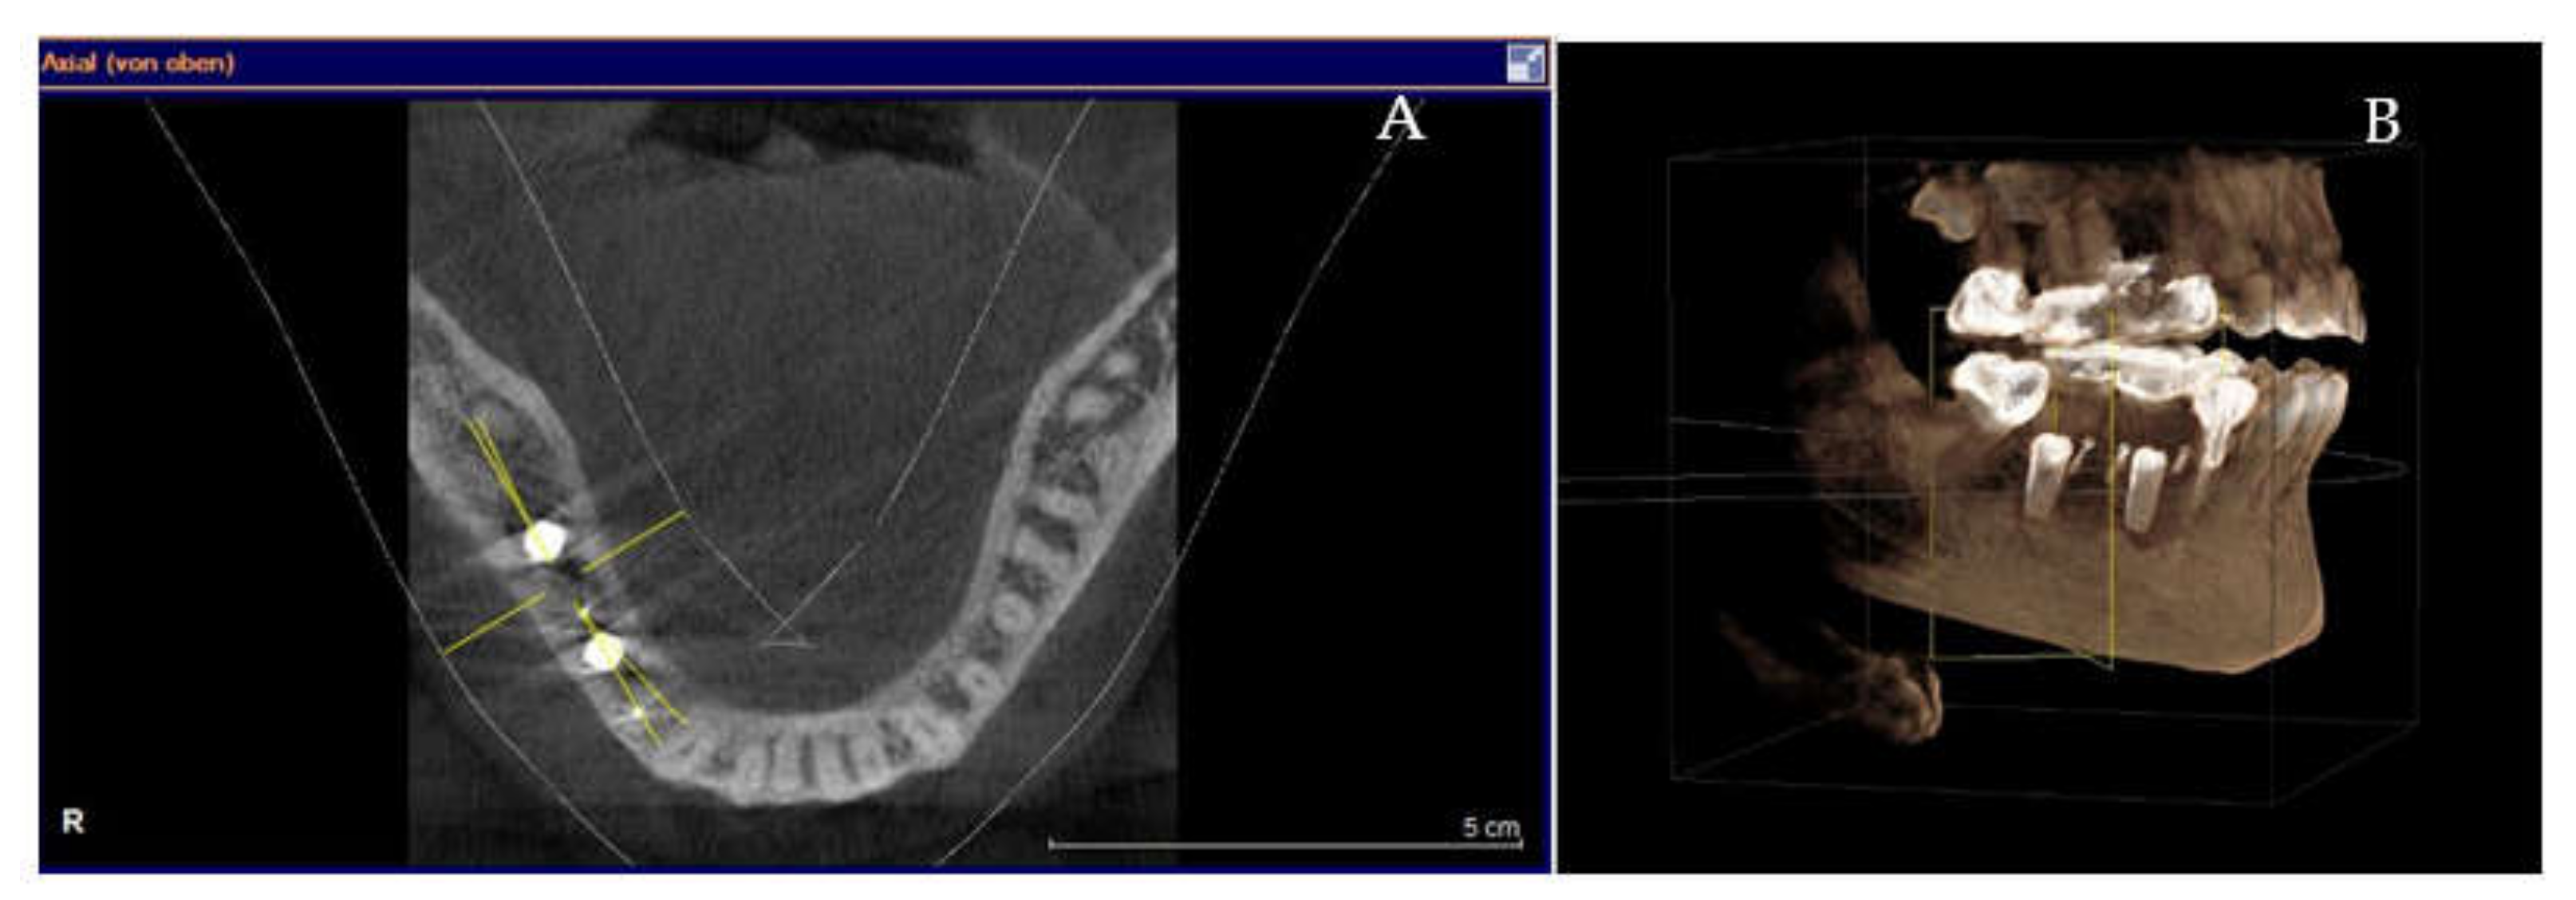

Clinical and CBCT aspects of patient from the test group, describing the stages of S-GBR technique and implant-prosthetic stage, are presented in Figure 1, Figure 2, Figure 3, Figure 4, Figure 5, Figure 6, Figure 7, Figure 8, Figure 9, Figure 10 and Figure 11. CBCT exam allows the evaluation of the horizontal alveolar bone defect and the position of the mandibular alveolar nerf (Figure 1A,B). Figure 1C,D show cross-sectional CBCT aspects of the implant sites. Figure 2 shows the narrowed mandibular alveolar bone with horizontal resorption. Figure 3 shows the exposed buccal surface of the alveolar ridge with severe horizontal resorption, after flap opening. The inserted implants (4.5 mm diameter, 11.5 mm length) and osteosynthesis screws (45° from the occlusal plan) are shown in Figure 4A. The placement of graft (autologous bone and xenograft) and collagen membrane is shown in Figure 4B. Figure 5A shows tension-free sutures, due to periosteal incisions alveolar ridge. Figure 5B shows clinical aspect at 7 months after surgery, with gingival tissue adherent on the reconstructed alveolar ridge. Figure 6 shows OPG aspect at follow-up of 7 months, with osseointegration of the dental implants. Figure 7A shows clinical aspect before osteosynthesis screws removal. Figure 7B shows clinical aspect after osteosynthesis screws removal. Figure 8A shows healthy peri-implant soft tissues. Figure 8B shows repositioning key for perfect position of abutments. Figure 10A,B show clinical aspects of implant-supported prosthetic restoration. Figure 11A,B show CBCT aspects of Osseo integrated dental implants at 24 months follow-up.

Figure 1.

(A,B) Pre-operative CBCT aspects. (A) Narrow residual alveolar ridge. (B) Analysis of the mandibular nerve position. (C,D) Pre-operative CBCT aspects (cross-sectional).